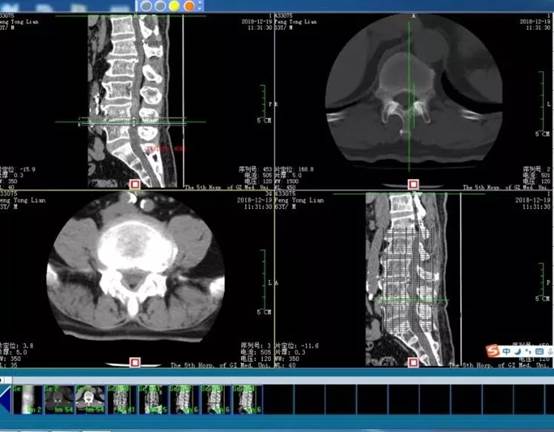

随后,给彭叔做了影像学检查,发现他存在腰椎退行性变;L3/4椎间盘突出;L4/5椎间盘膨出,L2/3、L5/S1椎间盘膨出。

需要注意的是,患者的腰椎:L1/2椎间盘突出,L2/3、L4/5椎间盘膨出,L3/4椎间盘明显突出并髓核脱出,对应水平硬膜囊前缘受压,L2、L4双侧神经根明显受压,骨性椎管继发性狭窄。